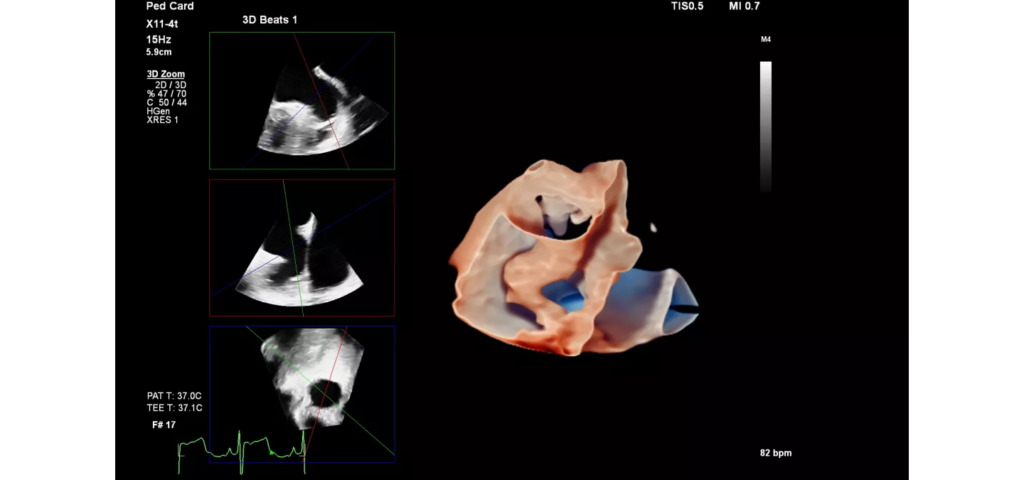

EPIQ CVx, our premium cardiovascular ultrasound system built on our innovative, modular, industry-leading ultrasound platform, has powerful AI-based capabilities and advanced diagnostic solutions to help you transcend today’s complexities and propel echocardiography into the next dimension. This enables you to achieve greater consistency, accessible innovation, smarter workflows, and easier scalability.

Epiq CVx